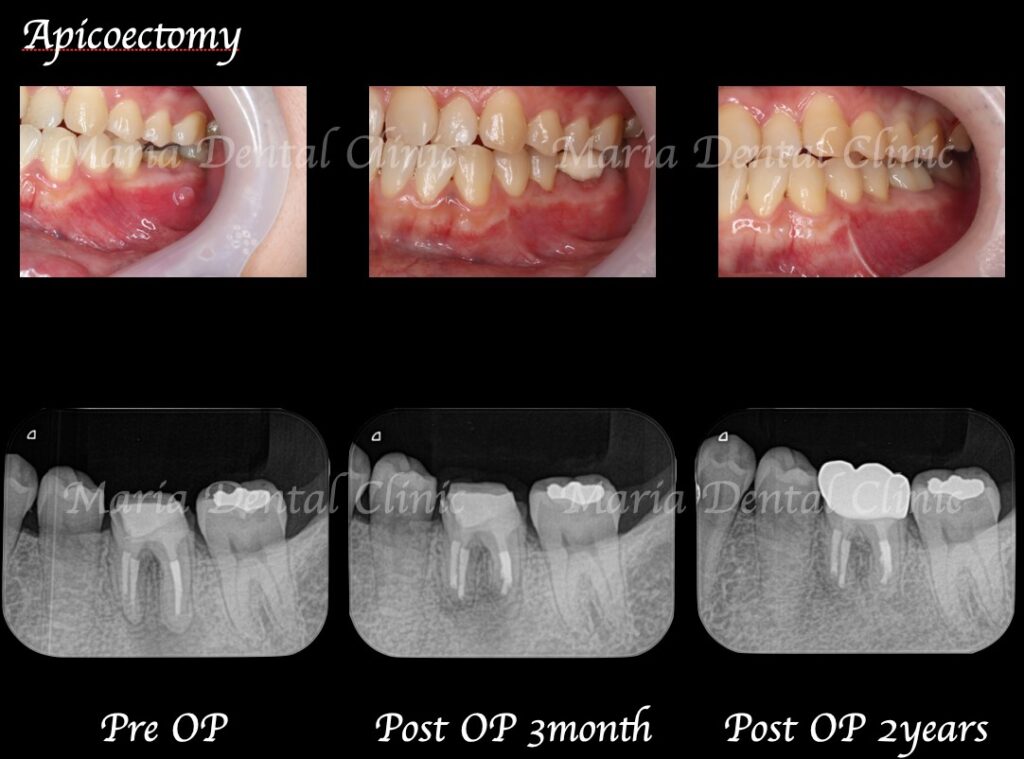

術後2週間で、術野の腫脹はほぼ消えて、術前に見られていた瘻孔(フィステル)の消失も確認できました。

3ヶ月後には瘻孔(フィステル)と、術前に訴えていた違和感は消失し、術野の歯肉の治癒も良好であることを確認しました。レントゲンでも、根尖部付近の骨の再生が認められたため、予後良好と判断しています。

今後は引き続き、1年間隔で経過観察を行なっていく予定です。